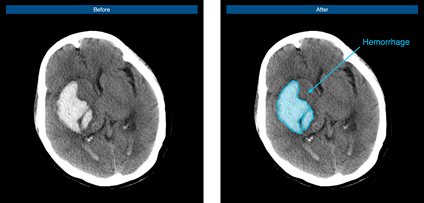

脑出血病例示意图

脑血管疾病领域作为推想医疗早期布局的重要疾病领域之一,在近年的北美放射协会年会(RSNA)上,公司便展示了首款脑卒中AI在研产品,通过不断研发和快速迭代“进化”,该产品已可快速判别是否存在出血、高效标注出血病变、准确定位和勾画出血区域、快速自动计算出血体积,从而提升医生的诊断速度,完善院端急救场景的智能分诊和流程管理,并最终为脑卒中患者赢得救治黄金期。